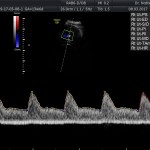

Modalidad de imagen ecográfica que permite evaluar flujos arteriales y venosos en estructuras fetales, placentarias y maternas obteniendo información valiosa sobre

- Riesgo fetal para cardiopatías congénitas y alteraciones cromosómicas (Evaluación de Ductus venoso).

Este modo ecográfico nos brinda datos importantes desde la 6ta a la 40ta semana de embarazo. Nosotros la utilizamos en todos nuestros exámenes ecográficos.